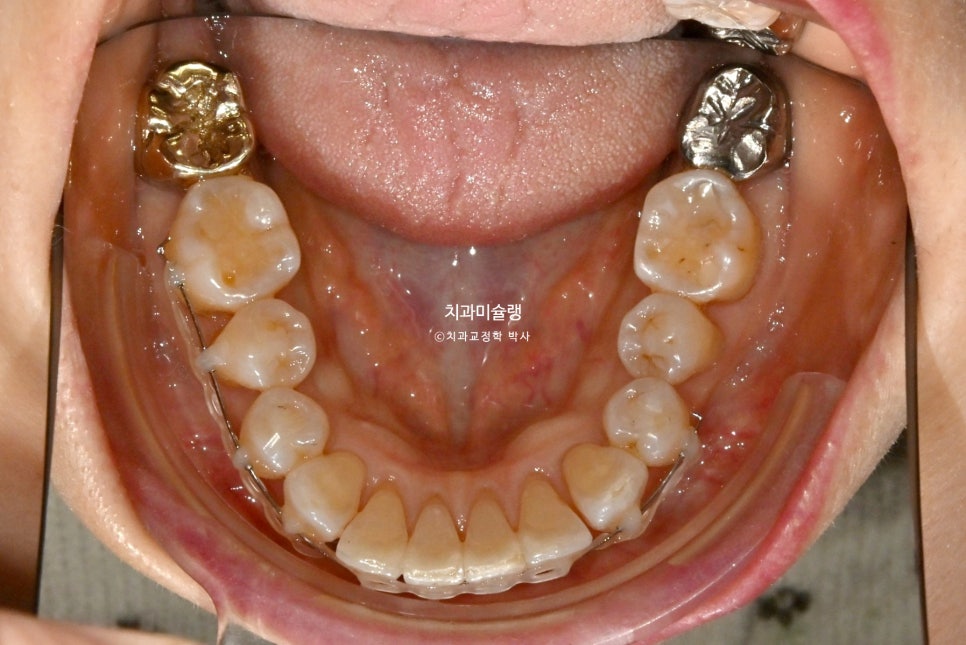

앞니 사이 블랙트라이앵글이 눈에 띕니다.

아래 송곳니중 한쪽이 덧니라 거꾸로 물리는 반대교합도 있습니다.

앞니 부분교정에서 치간삭제는 필수입니다. 과하지 않은 범위 내에서 시행하면 치료에 도움이 되죠.

장치는 작은어금니에서 작은어금니까지, 앞니 위주로 위아래 8개씩 붙였습니다.

치간삭제를 통해 블랙트라이앵글은 많이 줄었으며

고정식 유지장치까지 들어간 모습입니다.